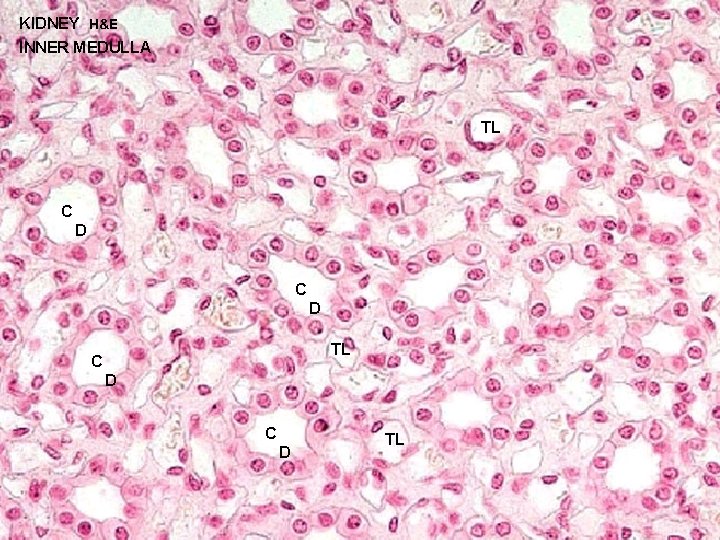

URINARY SYSTEM THE NEPHRON & COLLECTING DUCTS MEDULLA: OUTER ZONE 1 - STRAIGHT PORTIONS OF PROXIMAL TUBULE (THICK DESCENDING) 2 - STRAIGHT PORTIONS OF DISTAL TUBULE (THICK ASCENDING) 3 - THIN SEGMENTS OF LOOP OF HENLE (DESCENDING & 4 -ASCENDING) COLLECTING DUCTS INNER ZONE 1 - THIN SEGMENTS OF LOOP OF HENLE (DESCENDING & 2 -ASCENDING) COLLECTING DUCTS

URINARY SYSTEM THE NEPHRON & COLLECTING DUCTS MEDULLA: OUTER ZONE 1 - STRAIGHT PORTIONS OF PROXIMAL TUBULE (THICK DESCENDING) 2 - STRAIGHT PORTIONS OF DISTAL TUBULE (THICK ASCENDING) 3 - THIN SEGMENTS OF LOOP OF HENLE (DESCENDING & 4 -ASCENDING) COLLECTING DUCTS INNER ZONE 1 - THIN SEGMENTS OF LOOP OF HENLE (DESCENDING & 2 -ASCENDING) COLLECTING DUCTS

KIDNEY H&E INNER MEDULLA TL C D C D TL